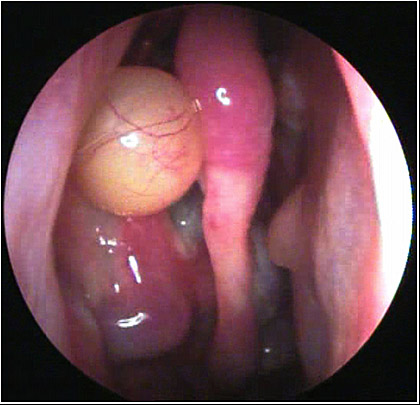

JFC Cuerpo extraño.